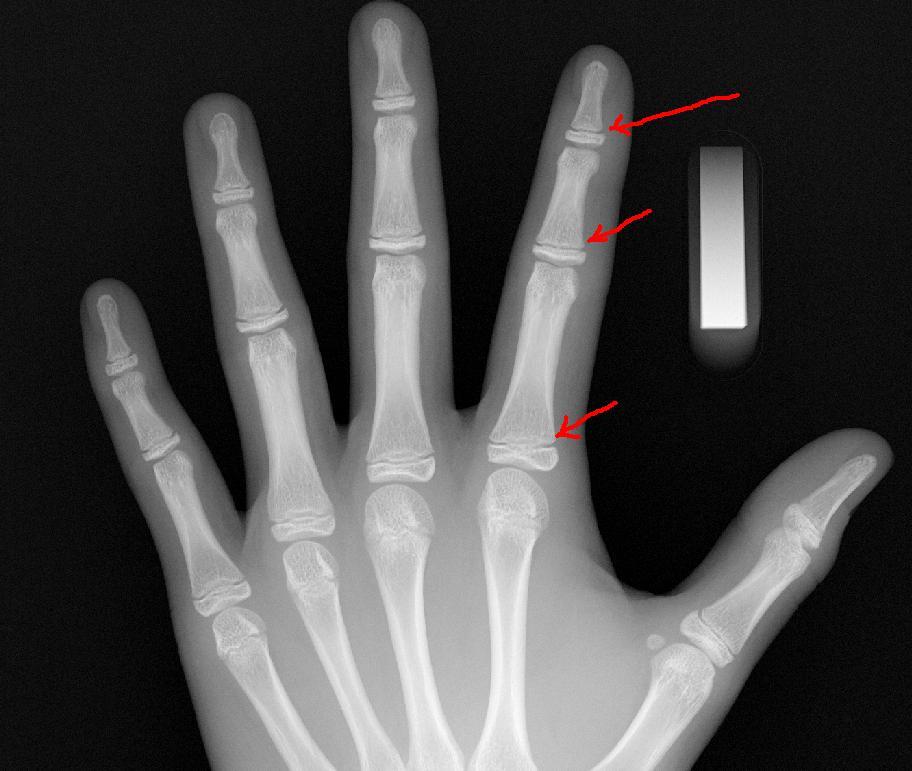

그 중 가장 많이 쓰이는 것이 위 사진처럼 손가락을 동그랗게 만들고

가운데 손가락을 뒤로 당겨 꺽으며 힘을 주면 팔목과 주변이 당기면서 아프면

성장판이 열려있고, 반응이 없으면 성장판이 닫힌거라고들 하지만

이는 잘못된 정보로서 성장판과는 전혀 무관한 내용이다

성장판이란 관절과 관절사이의 연골조직으로서

방사선 검사이전 자가체크로는 알 수 있는 방법은 전혀 없다.